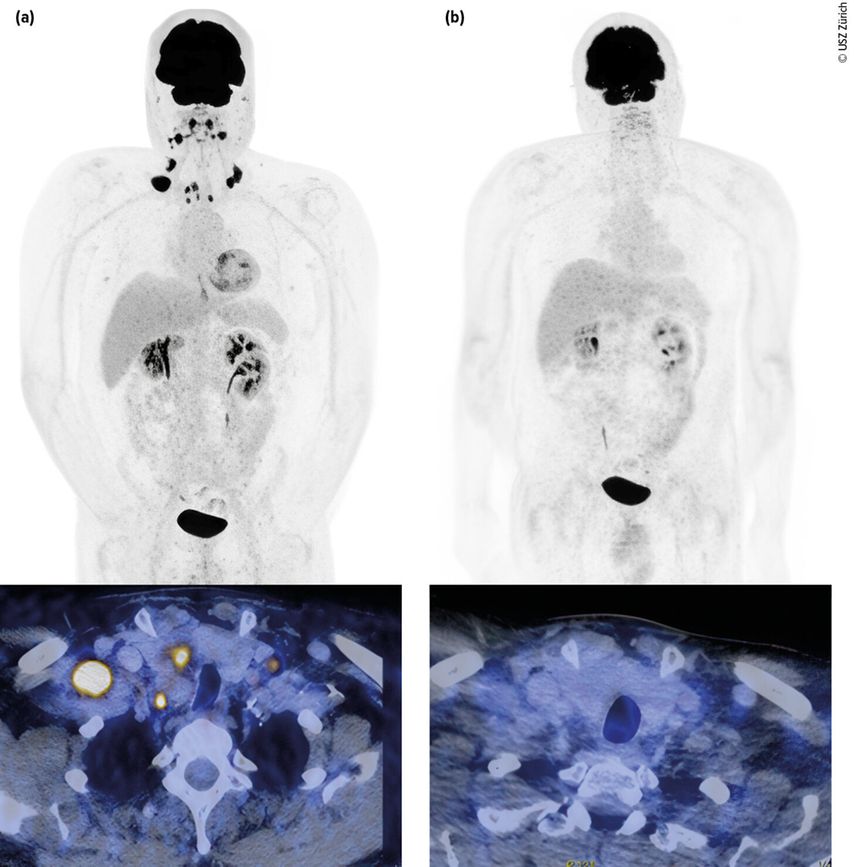

Abb. 1: Urothelkarzinom der Harnblase (initial cT3 cN3 cM0) mit metachron aufgetretener lymphogener Metastasierung. Staging mittels Computertomografie (PET-CT) mit Diagnose der lymphogenen Metastasierung (a, links). Erstes Restaging zwei Monate nach Therapiebeginn mit EV+P (b, rechts). Bildmorphologisch zeigt sich eine Komplettremission. Der Patient befindet sich weiterhin in anhaltender Remission. Bilder und Patient USZ Zürich

Das mediane OS konnte mit dieser Kombination signifikant auf knapp 34 Monate im Vergleich zu 16 Monaten mit alleiniger platinhaltiger Chemotherapie ± IO-Erhaltung gesteigert werden. In der Studie waren auch Patient:innen mit schlechterem Allgemeinzustand (bis ECOG 2) und Patient:innen mit reduzierter Nierenfunktion (GFR ≥30ml/min) eingeschlossen. Ein Update mit einem Follow-up von nun 2,5 Jahren zeigt, dass die Patient:innen, die eine komplette Remission (CR) erzielen, auch längerfristig in einer CR bleiben.6